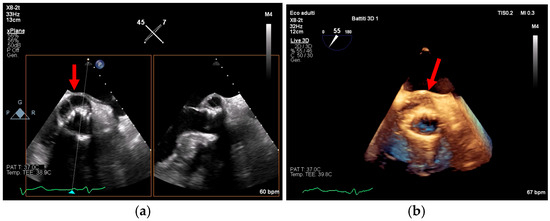

Multimodality Imaging in Infective Endocarditis: A Clinical Approach to Diagnosis

by Leonardo Brugiatelli, Francesca Patani, Carla Lofiego, Martina Benedetti, Irene Capodaglio, Pongetti Giulia, Francioni Matteo, Paolini Enrico, Nazziconi Marco, Kevin Maurizi, Furlani Giulia, Massari Arianna, Luciani Simone, Anselmi Benedetta, Gatti Chiara, Schicchi Nicolò, Fogante Marco, Tarsi Giovanni, Dello Russo Antonio, Di Eusanio Marco, Marini Marco and Fabio Vagnarelliadd Show full author list remove Hide full author list

Medicina 2025, 61(12), 2241; https://doi.org/10.3390/medicina61122241 - 18 Dec 2025

Infective endocarditis (IE) is a life-threatening condition with a rising incidence, demanding rapid and precise diagnosis. While echocardiography remains the cornerstone of initial evaluation, its limitations in complex cases—such as those involving prosthetic valves or cardiac devices—are well-known. This review synthesizes current evidence [...] Read more.

Infective endocarditis (IE) is a life-threatening condition with a rising incidence, demanding rapid and precise diagnosis. While echocardiography remains the cornerstone of initial evaluation, its limitations in complex cases—such as those involving prosthetic valves or cardiac devices—are well-known. This review synthesizes current evidence and guidelines to outline a practical, multimodality imaging approach for IE. We emphasize that integrating advanced techniques like cardiac computed tomography (CT) and [18F]-fluorodeoxyglucose positron emission tomography/computed tomography (FDG PET/CT) early in the diagnostic pathway, particularly in high-risk scenarios, significantly enhances diagnostic certainty, guides therapeutic decisions, and improves patient outcomes. A tailored imaging strategy, driven by clinical presentation and integrated within a multidisciplinary endocarditis team, is paramount for modern IE management. Full article

(This article belongs to the Special Issue Diagnosis and Treatment of Valvular Heart Diseases)

Show Figures

Figure 1